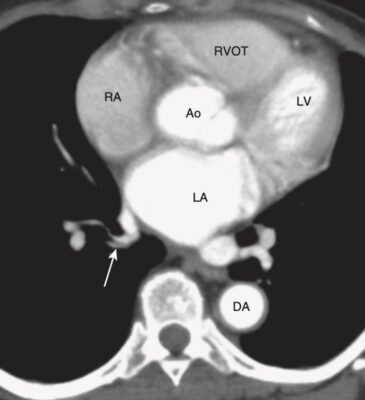

Mức tim cao (Hình 9)

- Ở mức này, có thể xác định được nhĩ trái, nhĩ phải, gốc động mạch chủ và đường ra của thất phải (right ventricular outflow tract, RVOT).

- Tâm nhĩ trái chiếm phần sau và trung tâm của tim. Có thể thấy một hoặc nhiều tĩnh mạch phổi đổ vào nhĩ trái.

- Tâm nhĩ phải tạo thành bờ phải tim và nằm ngay bên phải của nhĩ trái.

- Đường ra của tâm thất phải nằm trước, bên và trên so với gốc của động mạch chủ. Van động mạch phổi nằm trước, bên và trên van động mạch chủ .